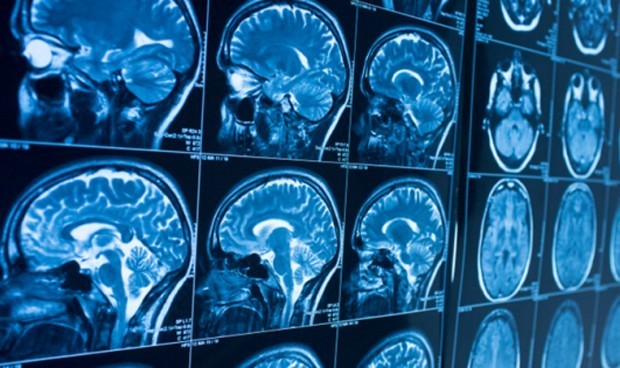

Las resonancias magnéticas a los 45 años revelaron algunos cambios pequeños pero significativos en los cerebros de las personas que tenían mayores exposiciones al plomo medidas a los 11 años.

Por cada 5 microgramos por decilitro más de plomo que tenían cuando eran niños, los participantes del estudio perdieron un promedio de 2 puntos de CI a los 45 años. También tenían un poco más de 1 centímetro cuadrado menos de superficie cortical y 0,1 centímetro cúbico menos de volumen en el hipocampo. que juega un papel en la memoria, el aprendizaje y las emociones.

Los participantes con la mayor exposición infantil al plomo también demostraron déficits estructurales en la integridad de la materia blanca de sus cerebros, que es responsable de la comunicación entre las regiones del cerebro.